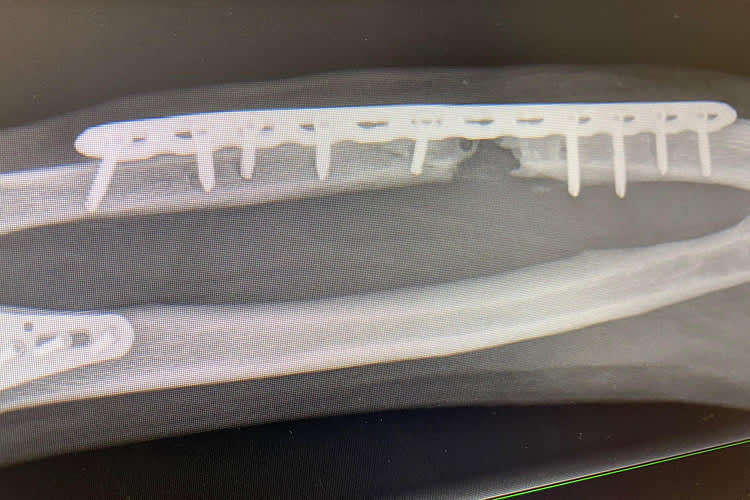

Horst Saiger: «Eineinhalb Zentimeter Knochen fehlen»

Fünf Monate nach seinem verhängnisvollen Sturz veröffentlichte Horst Saiger auf Facebook ein Foto, das zur Hoffnung auf vollständige Genesung Anlass gibt. Vor dem Steirer liegt aber noch ein langer Weg.

"An den Unfallhergang habe ich nur bruchstückhafte Erinnerungen", erzählte der dreifache Familienvater im Gespräch mit SPEEDWEEK.com. "Am Ende der Start-Ziel-Geraden hat meine Vorderradbremse versagt. Ich habe dann mit versucht, mit der Hinterradbremse mein Tempo zu reduzieren. Knapp vor der Streckenbegrenzung bin ich gestürzt. Laut Data-Recording hat mich mein Motorrad mit 110 km/h getroffen." Die Liste der Verletzungen, die von den behandelnden Ärzten festgestellt wurden, war lang und ging von zahlreichen Knochenbrüchen an den Extremitäten über Serienrippenbrüchen, die auch die Lunge in Mitleidenschaft zogen, eine lädierte Leber bis zu Blutungen im Kopf. Aber vor allem ein offener Unterarmbruch sollte in Folge wegen einer Infektion über Wochen zu massiven Problemen und weiteren Spitalaufenthalten führen. "Im Arm haben sich Bakterien abgelagert und zu einer schweren Infektion geführt. Durch die Antibiotika und den Schmerztabletten habe ich in wenigen Tagen sieben Kilo abgenommen. Die Metallplatte musste entfernt und durch eine neue ersetzt werden. Jetzt fehlen an der Bruchstelle eineinhalb Zentimeter Knochen. Nach insgesamt 18 Wochen wird kontrolliert, ob sich diese Lücke von selbst schließt oder ob ich eine Knochentransplantation benötige."

Mittlerweile ist der 49-jährige Saiger auf dem Weg der Besserung, auch wenn seine Leidensgeschichte noch lange nicht zu Ende ist. "Es geht mir von Tag zu Tag spürbar besser. Bis auf den besagten linken Unterarm sind alle Knochenbrüche verheilt. Ich kann mit meiner Familie bereits wieder längere Spaziergänge unternehmen und ich merke, dass ich langsam wieder zu Kräften komme", so der erfolgreiche Road Racer.